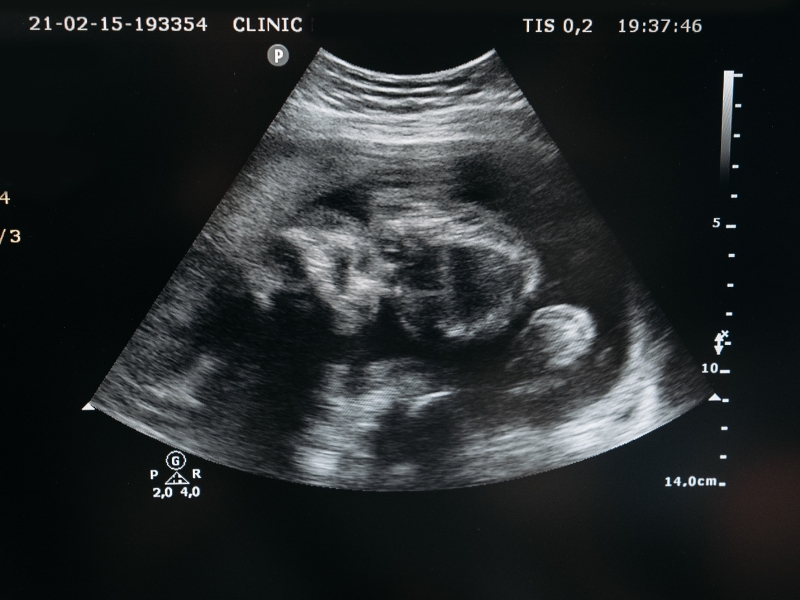

A ultrassonografia pélvica ginecológica é uma ferramenta essencial para avaliar a saúde do sistema reprodutivo feminino. Ela permite identificar condições como cistos, miomas ou anomalias uterinas de forma não invasiva e precisa.

Durante o exame, ondas sonoras geram imagens detalhadas dos órgãos internos. Este tipo de ultrassom ajuda médicos a diagnosticar problemas com rapidez, proporcionando um acompanhamento eficaz da saúde da mulher em diferentes fases da vida.